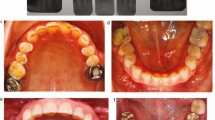

The palatal protective dressing was removed after one week in both groups [24]. Wound healing was monitored via clinical photographs taken at 1, 2, 3, and 6 weeks postoperatively (Fig. 2) [26].